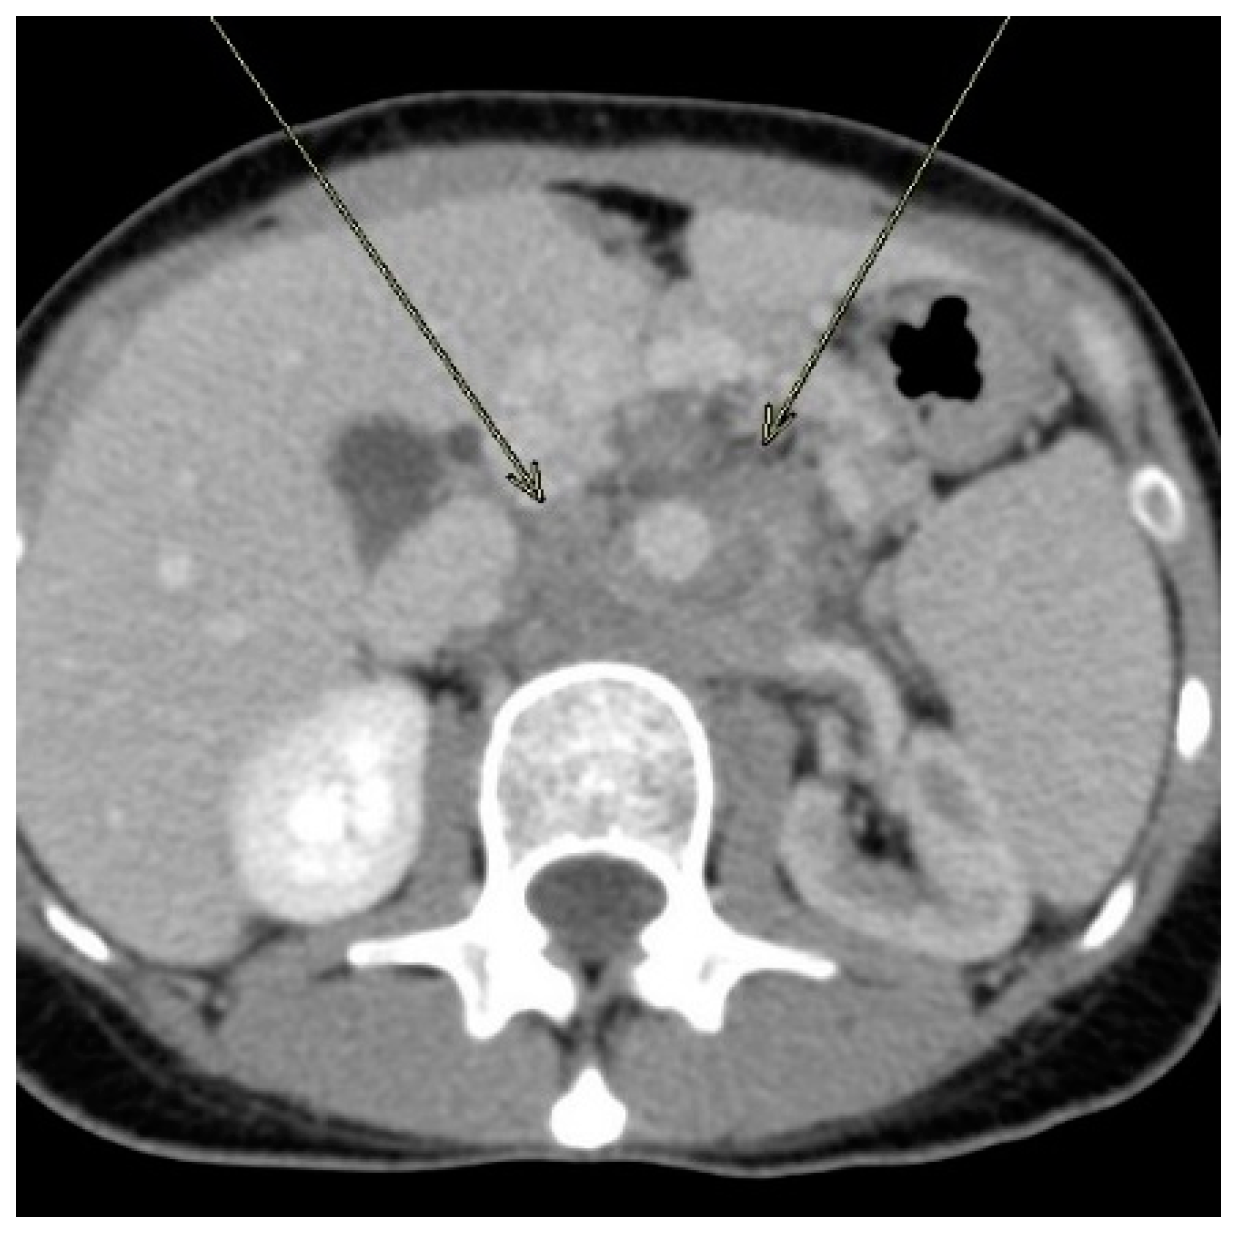

Invasive Basidiobolomycosis Presenting as Retroperitoneal Fibrosis: A Case Report

2. Case Report